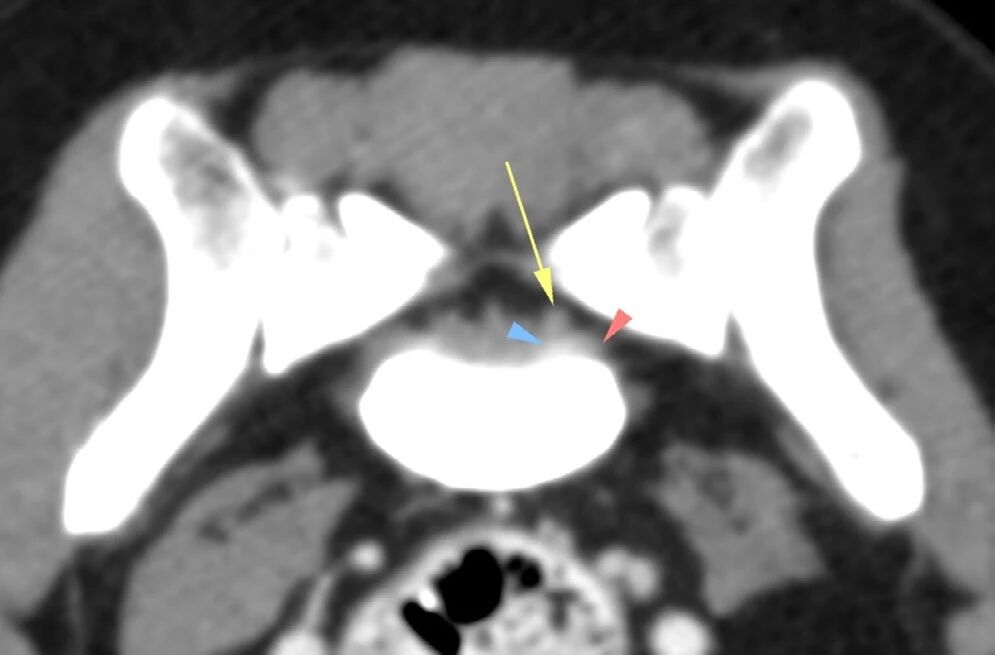

可见左后肢及臀部肌肉明显萎缩,腰骶部椎管内及增大的左侧L7神经根处出现轻度造影剂强化(下图)。据此推测左侧L7/S1椎间隙存在脊神经炎症,导致神经源性肌肉萎缩。

↑ L7-S1脊柱的CT图像(横截面,软组织重建,经过对比后),显示了增大的神经(箭头)和周围组织的轻度对比增强(三角)。